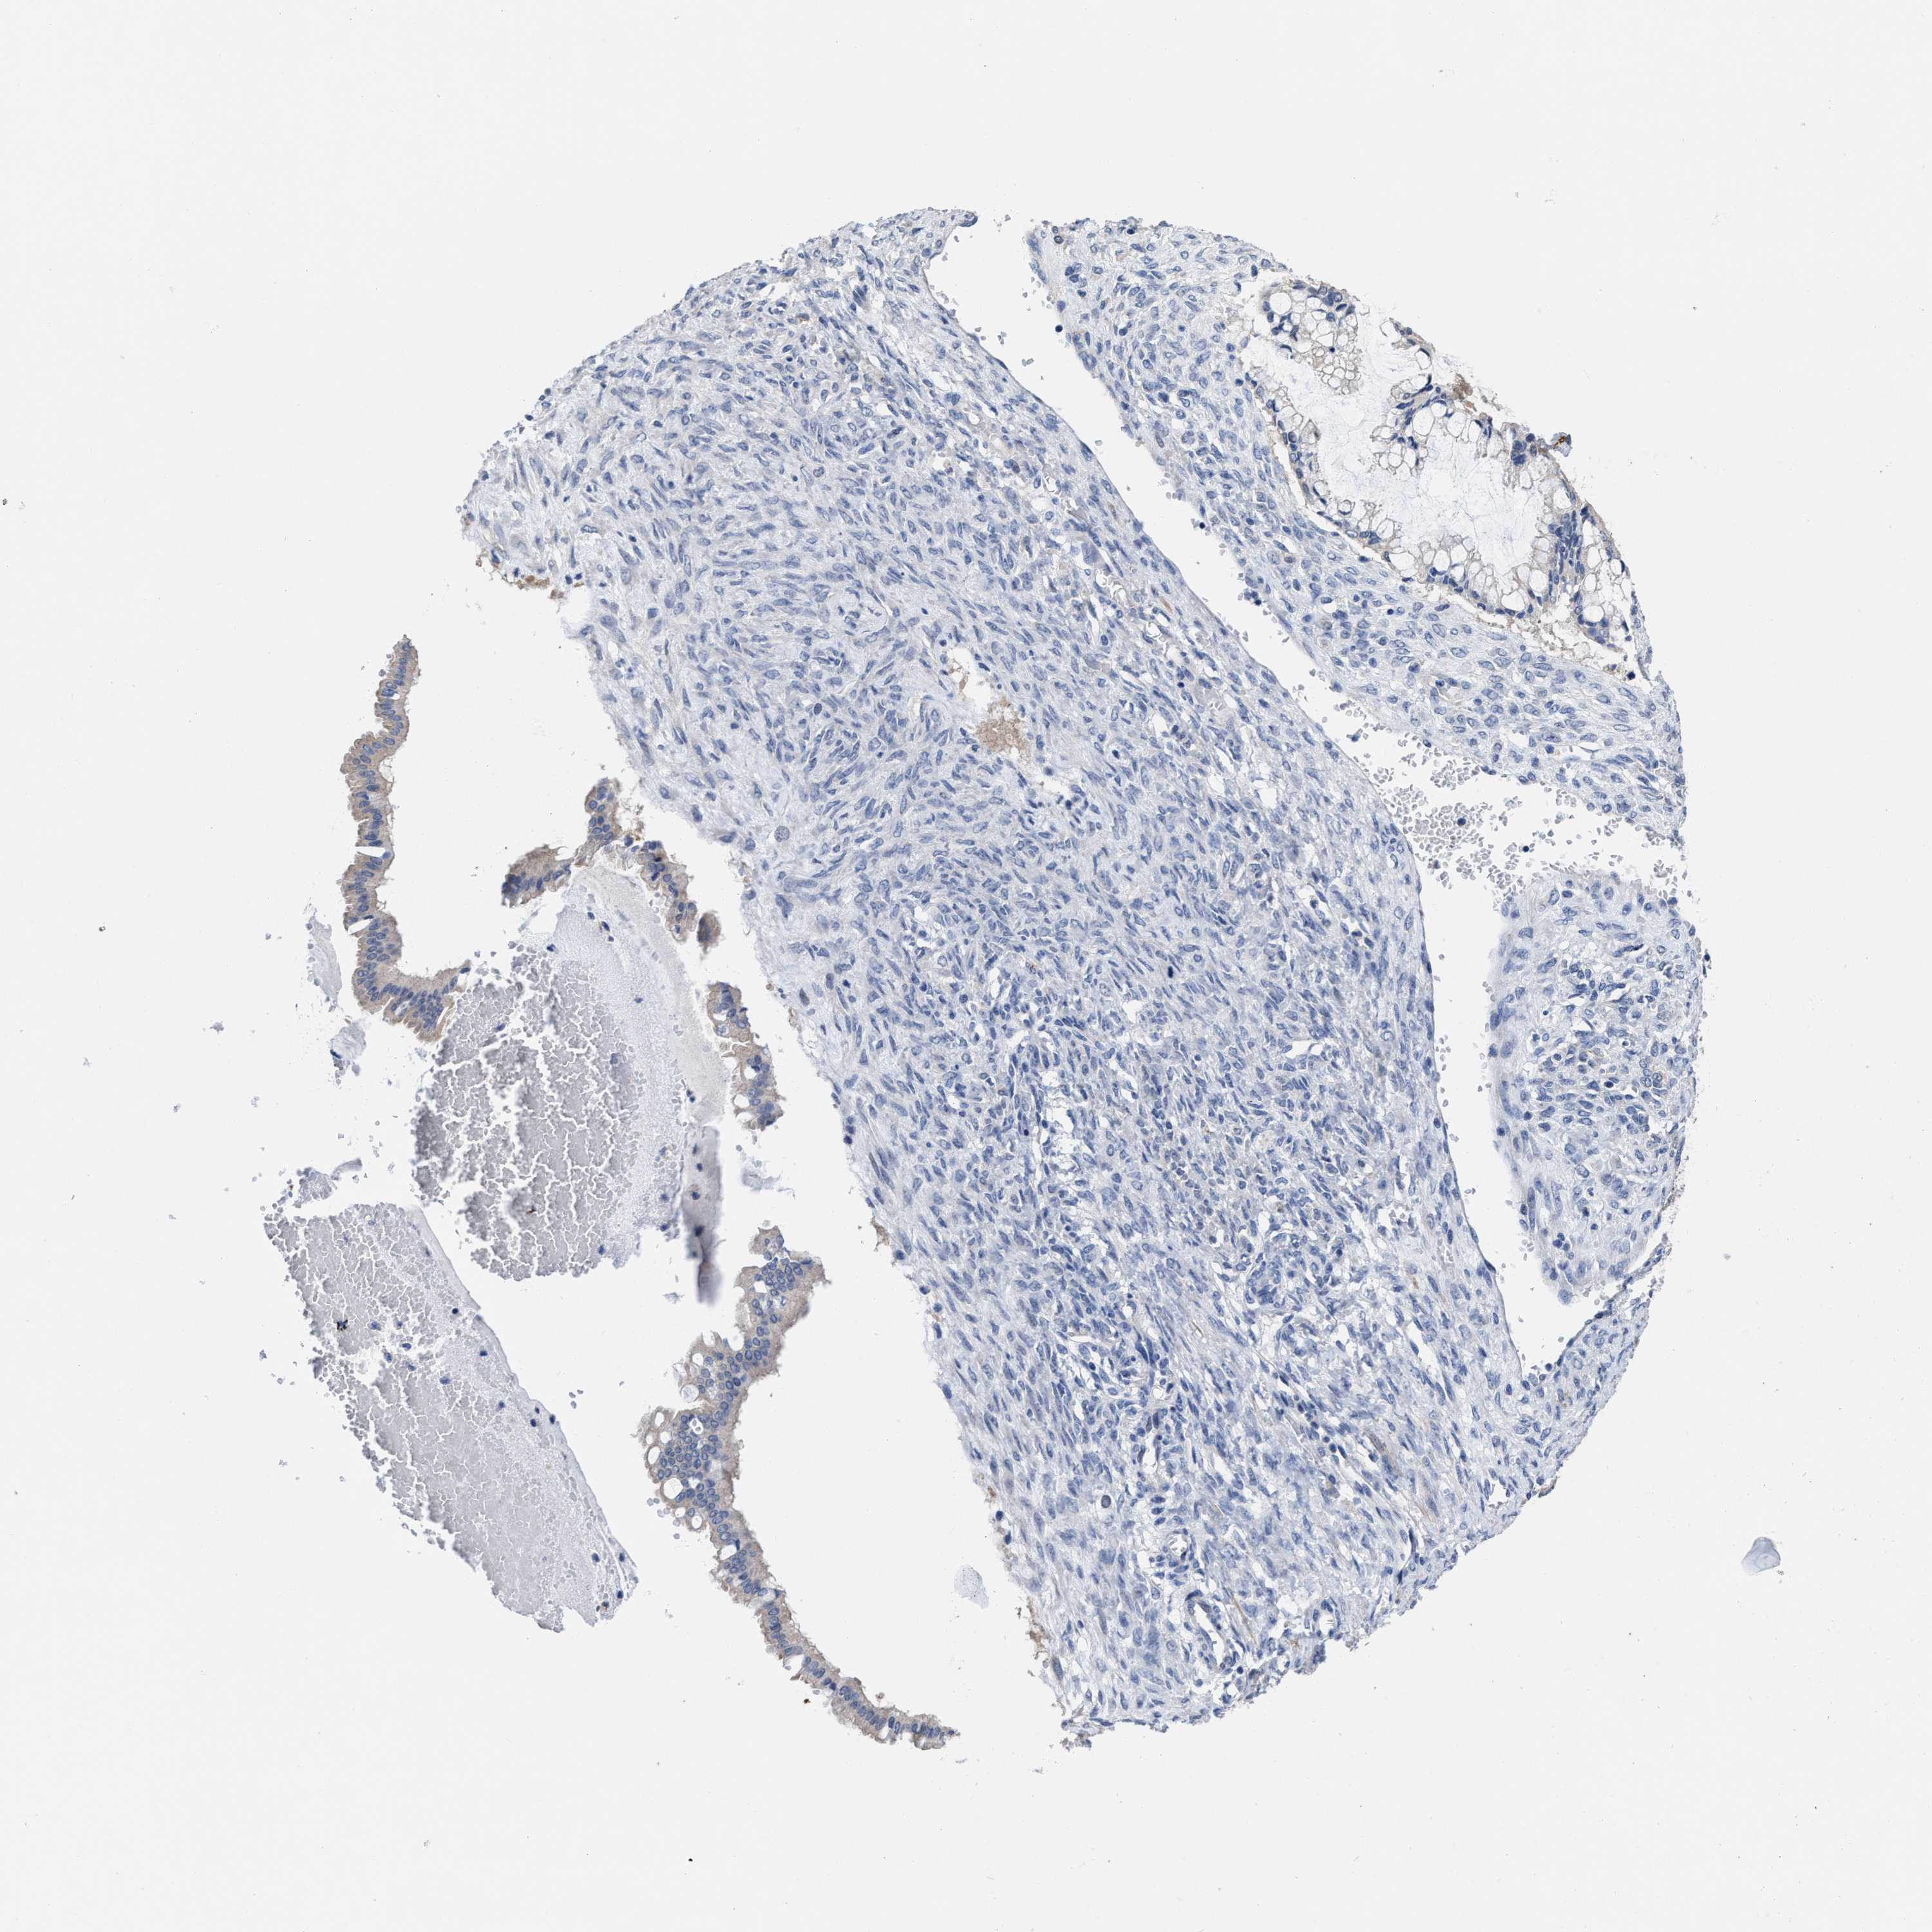

OVARIAN CANCER - Protein expressioni

A mouse-over function shows sample information and annotation data. Click on an image to view it in a full screen mode. Samples can be filtered based on level of antibody staining by selecting one or several of the following categories: high, medium, low and not detected. The assay and annotation is described here.

Note that samples used for immunohistochemistry by the Human Protein Atlas do not correspond to samples in the TCGA dataset.

Antibody stainingi

Antibody staining in the annotated cell types in the current human tissue is reported as not detected, low, medium, or high, based on conventional immunohistochemistry profiling in selected tissues. This score is based on the combination of the staining intensity and fraction of stained cells.

Each image is clickable and will lead to virtual microscopy that enables deeper exploration of all samples and also displays staining intensity scores, fraction scores and subcellular localization as well as patient and tissue information for each sample.

Antibody HPA018537

Antibody HPA018820

Cystadenocarcinoma, serous, NOS

Carcinoma, endometroid

Cystadenocarcinoma, mucinous, NOS

Carcinoma, NOS